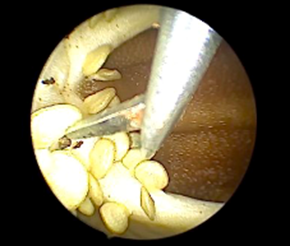

Instruments and Technique: Each training set up had a 2.9mm 30° hysteroscope with a 5mm operative sheath, connected to a camera control unit and monitor, with an LED light source as the primary operating instrument. Hysteroscopic scissors and graspers were the instruments available for use. Bipolar loop resectoscopes connected to underwater diathermy electrosurgical generators were also provided. Distension media used was 0.9% normal saline irrigated with a Hysteromat Ò (Karl Storz SE & Co KG Tuttlingen Germany) providing the facility to control inflow, outflow and fluid deficit estimation like real surgery. The trainees were guided on correct assembly and handling of the hysteroscope and then underwent hands on training on the standard bell pepper model with a set of prescribed exercises under the guidance of proctors. The participants were asked to perform diagnostic hysteroscopy first to build hand-eye coordination and understand the movement of the hysteroscope. The trainees next used scissors and graspers on the capsicum seeds to simulate polypectomy, scissors to simulate septum resection and metroplasty and used the natural crevices of the pepper to practice tubal cannulation (Figure 1 – 6).

Figure 4: Septum Resection

Figure 5: Lateral Metroplasty